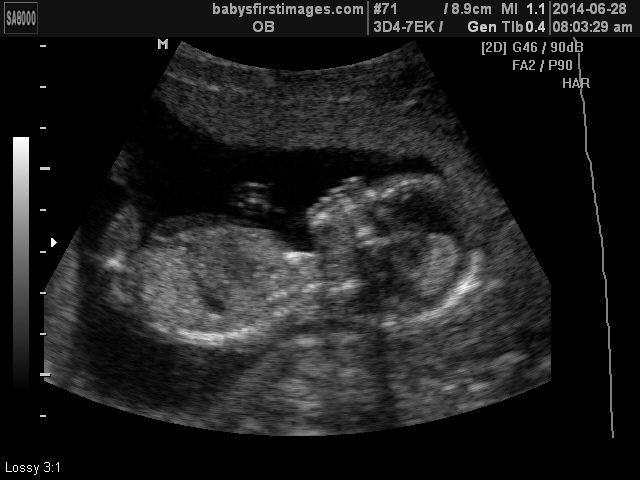

So I’m a couple of days late on the blog update… but it’s official – we’re having a girl! I’m going to steal the words from one of my aunts… I love when God’s plans fit with our desires. Amen! It is such a blessing that we’ll get to experience raising boys and a girl, and I truly feel as though our family will be complete come December. And I am especially excited for my husband because I know how much he wanted a daughter. I can’t wait to see him get to live that dream of having daddy’s little girl – it is going to be awesome!